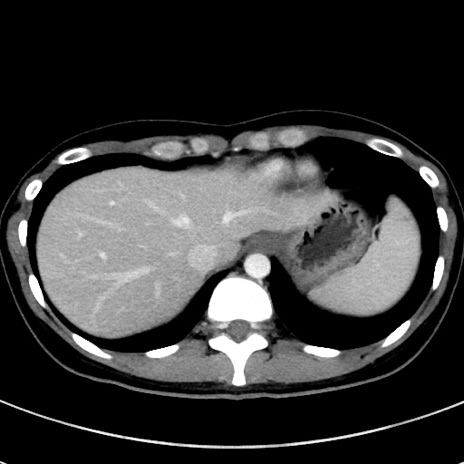

症例17(横断像)

【症例】20歳代女性

【主訴】嘔吐、下腹部痛

【現病歴】昨日夕食後に嘔吐し下腹部痛が出現。本日になっても嘔吐持続し改善しないため来院。

【身体所見】意識清明、BT 37.2℃、BP 108/67mmHg、腹部:平坦、やや硬、下腹部正中から右にかけて圧痛あり、反跳痛軽度あり、tapping pain(+)。

【データ】WBC 13600、CRP 14.94